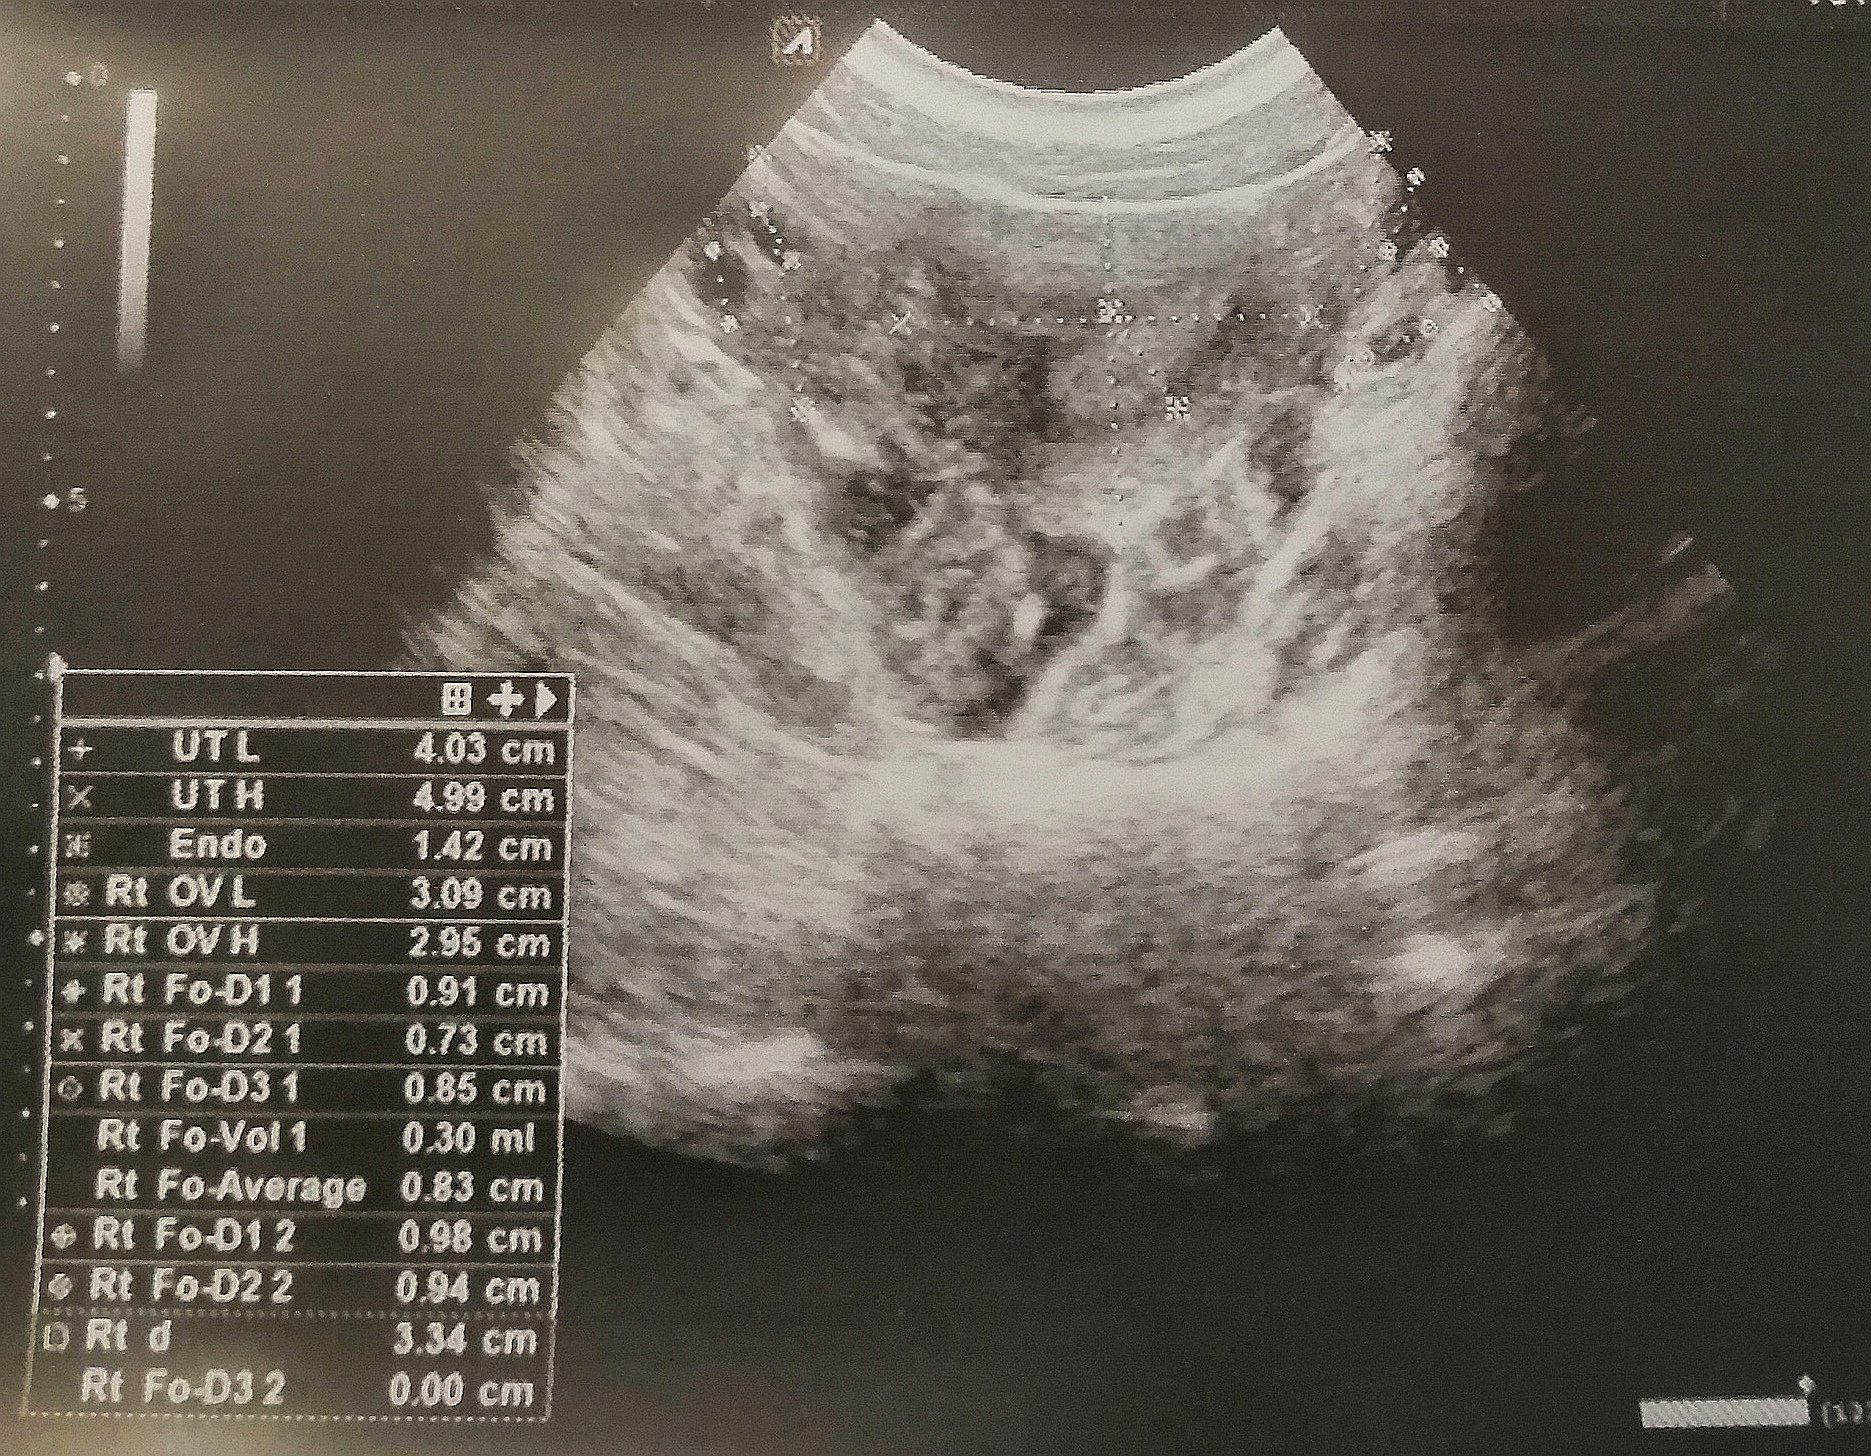

Дами, здравейте,

Днес, след дълги години с брутално болезнена  менструация и овулация от десния яйчник, най-накрая някой ми каза ендометриоза.. На 32г. съм. Пила съм 7 години противозачатъчни, изписвани от лекарите, като ги спрях преди 3 на своя глава. Имах отвратотелни странични ефекти накрая..

Та по същество, предложиха ми два варианта: проклетите хапчета пак или абразио.. Малко съм в шок, нямам никаква идея какво да направя.. Прикачвам и снимката от ехографа, ще съм благодарна някоя от вас да ми помогне с резултатите върху нея, тъй като явно съм се гипсирала и помня тук там какво ми каза лекарката.. Всъщност всичко коментирано ще ми е от полза..

А защо абразио, лапароскопия се прави за премахване на ендометриозна киста. После се изследва материал, за да потвърдят наистина.

Само на ехограф няма как да кажат дали със сигурност е такава кистата, ако това на снимката е киста всъщност, а не някое срастване.

Това ми прилича на сраствания. Лапароскопията е най-доброто решение, защото ще се видят повече евентуално засегнати участъци. Бих сменила АГ с такъв, който има опит с ендометриозата генерално.